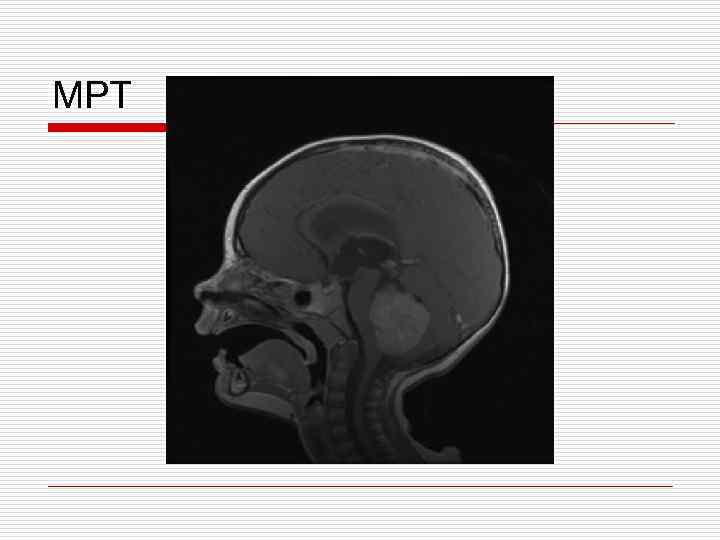

Клинический пример o Девочка В. , 13 лет – атаксия в течении 1 месяца o В течении 2 недель нарастание головных болей o Рвота по утрам n Темпиратура тела нормальная n Нет изменений в ОАК, ОАМ и БХ; педиатр исключает соматическую патологию

МРТ

Опухоли головного мозга у детей Морфологически гетерогенны * клетки-предшественники: glial, neural, other, combination * локализация: ЗЧЯ: 50% супратенториально: 50% * Клиника зависит от: локализации возраста

Опухоли мозга у детей o Инфратенториальная локализация 50% чаще < 6 лет o Супратенториальная локализация 50% чаще > 8 лет